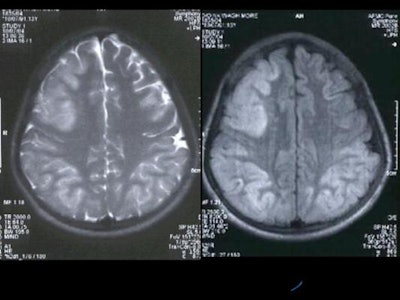

Hyperintensity was also present in the posterior pons and quadrigeminal plate on T2W and FLAIR images, appearing mildly hypointense on T1WI. [Figure 3]